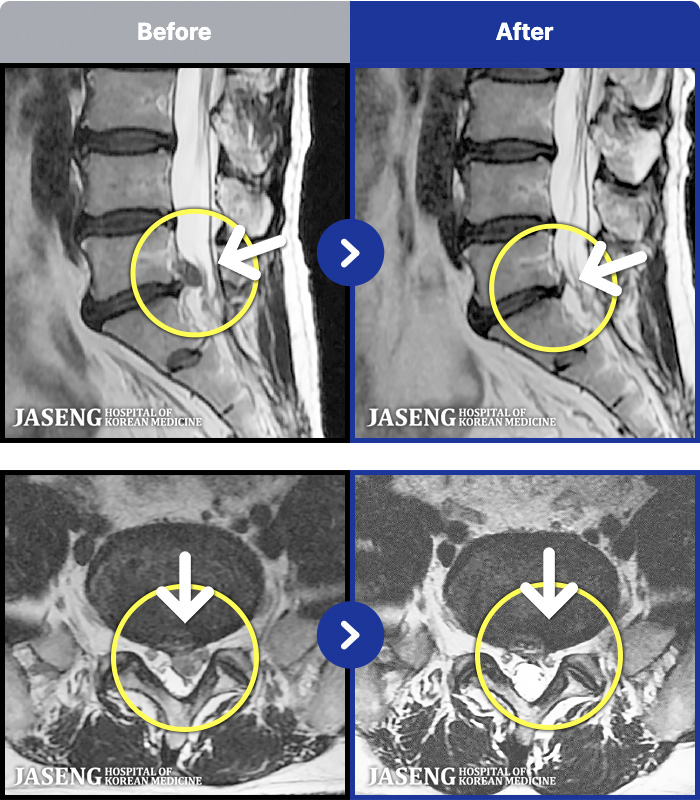

65 MRI ũ ʸ Ȯϼ.